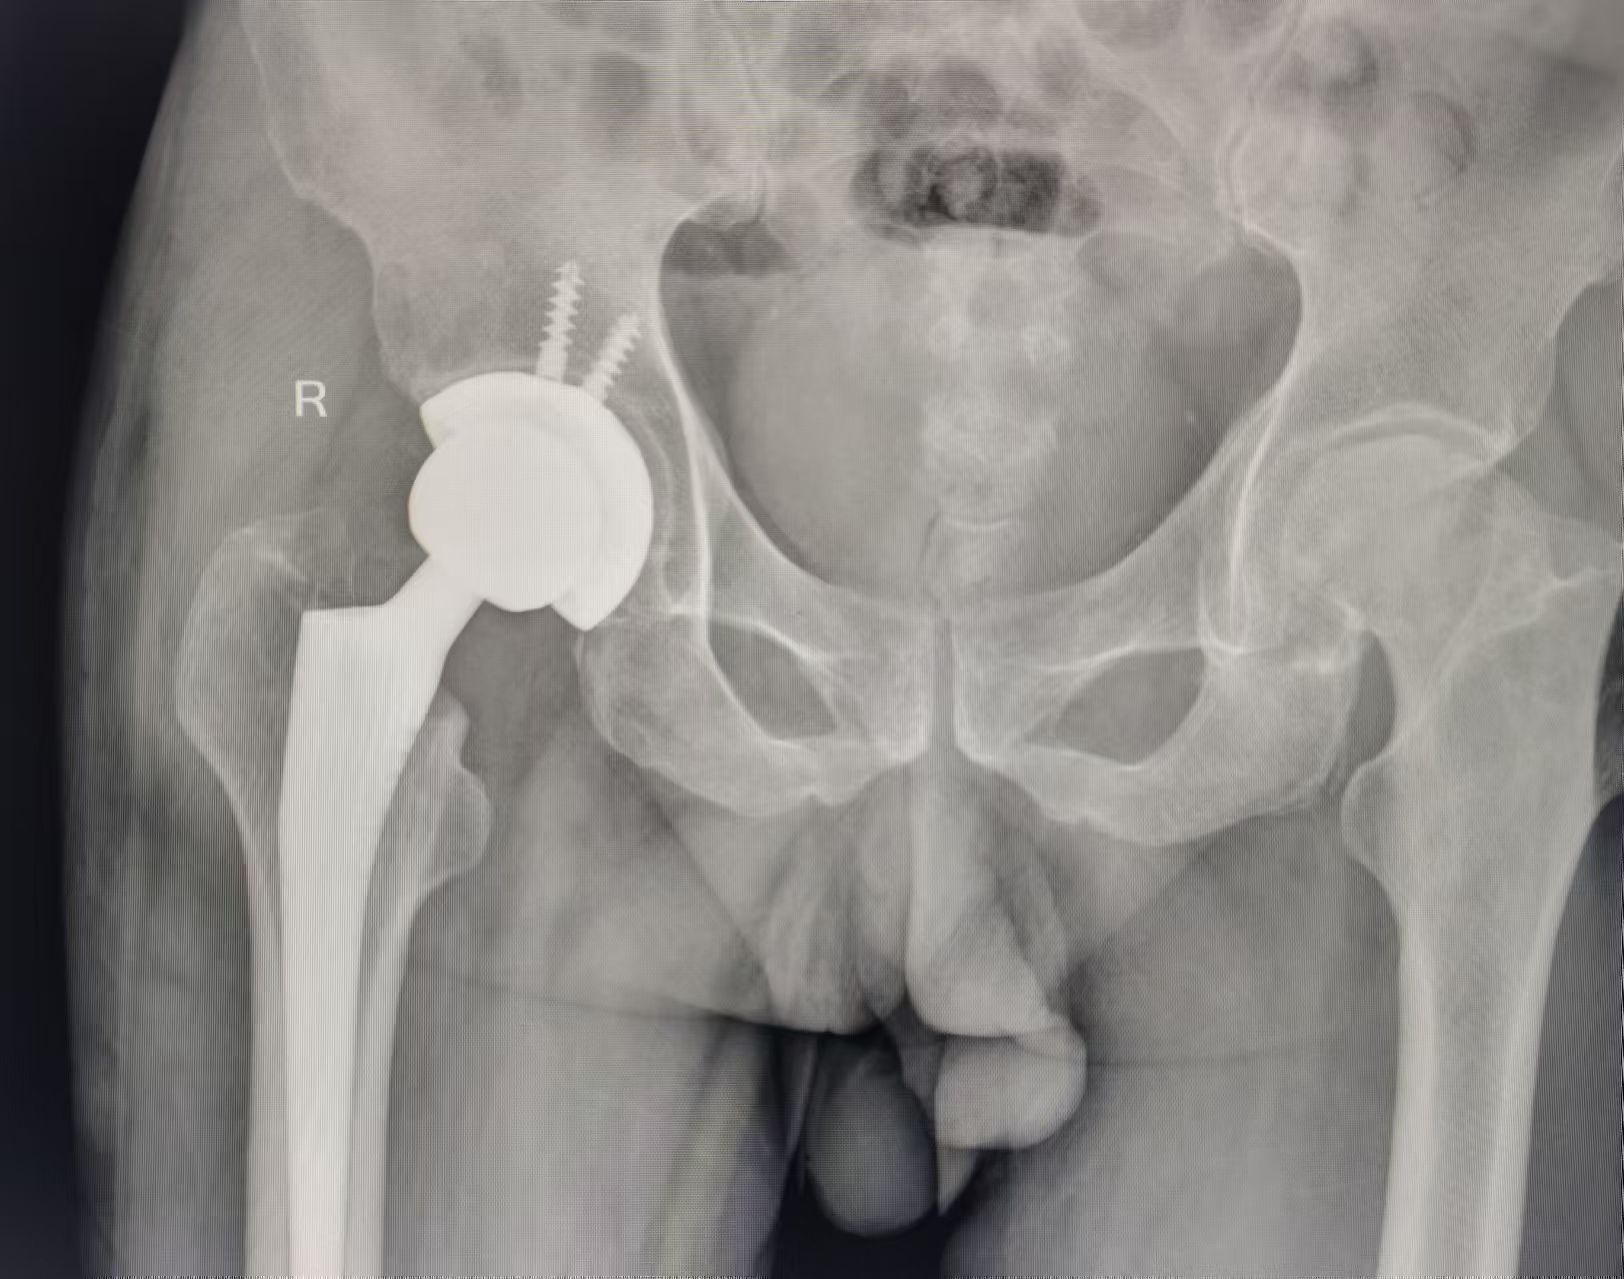

近日,创伤关节一病区收住了一位由于长期双髋关节疼痛伴活动受限的股骨头坏死(晚期)患者,右髋关节疼痛重,右侧屈髋屈膝、内收外展、内旋外旋重度受限,范洪伟主任医师主持全科讨论及其阅片后,决定为患者行「右全髋关节置换术」。

创伤关节手术团队与麻醉团队协同合作,患者手术非常成功,术后范洪伟主任医师基于「肝主筋、肾主骨,气血同源」理论,根据患者病情进行辨证论治,以八珍汤、六味地黄汤等为底方加减化裁,加速患者的康复。

患者术后第 2 天即可下地站立,第 3 天指导患者在助步器帮助下开始行走,后期罗阳东主治医师通过微信、电话等方式进一步指导患者功能锻炼,术后 1 月患者已基本可以适应性行走,极大程度上缓解了患者痛苦。